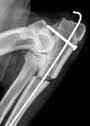

- Die Operationen Knie während Patellaluxationen Oder von Kreuzbandrisse die zu den ersten Pathologien in der Hundeorthopädie geworden sind.